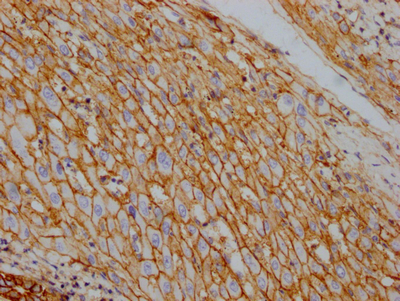

IHC image of CSB-RA796310A0HU diluted at 1:100 and staining in paraffin-embedded human kidney tissue performed on a Leica BondTM system. After dewaxing and hydration, antigen retrieval was mediated by high pressure in a citrate buffer (pH 6.0). Section was blocked with 10% normal goat serum 30min at RT. Then primary antibody (1% BSA) was incubated at 4℃ overnight. The primary is detected by a Goat anti-rabbit IgG polymer labeled by HRP and visualized using 0.05% DAB.